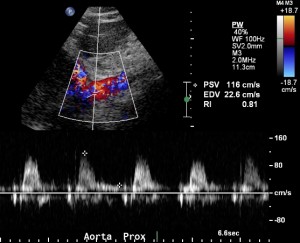

The midline approach is ideal for obtaining blood flow velocity in the proximal aorta. This velocity is later used to calculate the renal to aorta flow ratio. An increased ratio suggests significant renal artery stenosis. The velocity in the proximal aorta should be measured at the level of the origin of the superior mesenteric artery. The superior mesenteric artery is often easier to identify when the aorta is elongated as its course is often parallel to that of the aorta. Sampling of the superior mesenteric artery waveform should show a high resistant waveform, if the patient has indeed fasted.

The next step is to identify the renal arteries. Each renal artery should be sampled in its origin and proximal, mid and distal portions. The distal portion of the renal artery is often difficult to obtain from the midline even in easy renal artery ultrasound. The proximal portion is difficult to obtain from the flank and therefore effort should be made to obtain it from the midline.

Sometimes the images are less than optimal. If there is uncertainty, images should not be acquired. However, if the renal artery can be identified coming in from the rest of the noise, then it can be sampled: